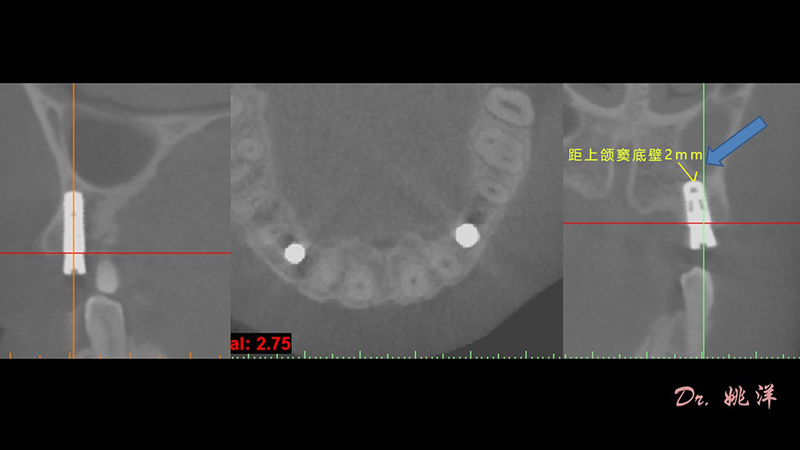

根據(jù)患者CT顯示,使用種植導(dǎo)航軟件設(shè)術(shù)前手術(shù)方案??紤]到患者拒絕手術(shù)摘除上頜竇囊腫等因素,此次手術(shù)選用了Straumann骨水平4.10*8.0mm的植體,植體末端位點(diǎn)設(shè)計(jì)距上頜竇底壁2mm處的同時(shí)兼顧種植方向和修復(fù)間隙,來(lái)達(dá)到理想的效果。

導(dǎo)航下精細(xì)分配修復(fù)間隙,精細(xì)規(guī)劃植入方向,避開(kāi)上頜竇底,精確植入

從術(shù)后CBCT顯示可以看出,手術(shù)操作中完美地避開(kāi)上頜竇底,并兼顧了正確的種植方向和修復(fù)間隙